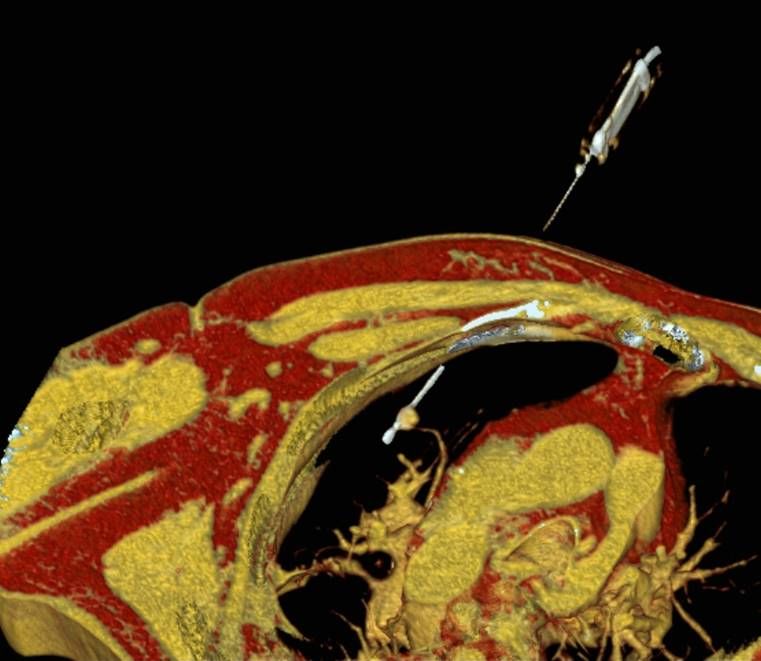

Präoperative Tumormarkierung

Eine Voraussetzung für die vollständige chirurgische Entfernung von Knochen- und Weichteiltumoren ist die präzise Erkennung der Tumorausdehnung und der Tumorgrenzen. Mit der Kernspintomographie (MRT) kann das Tumorgewebe exzellent von gesundem Gewebe abgegrenzt werden und somit die Ausdehnung vor der Operation bestimmt werden. Nach der kernspintomographischen Bestimmung der Tumorausdehnung werden unter kontinuierlicher MRT-Bildgebung die Grenzen des Tumors markiert. Die Marker werden mit einer Nadel ins angrenzende gesunde Gewebe eingebracht. Die Markierung kann am Tage vor der Operation durchgeführt werden. Alternativ ist die Tumormarkierung auch mit anderen bildgebenden Verfahren möglich, z.B. mit der Computertomographie oder dem Ultraschall.

Abbildung: Bei diesem Patienten wurde ein im Röntgen nur schlecht sichtbarer Knochentumor vor der Operation unter MRT-Kontrolle mit kleinen röntgendichten Spiralen („Coils“) markiert. Damit hat der Operateur eine optimale Darstellung des Tumorbereichs bzw. der Tumorgrenzen und kann gezielter, schonender und effektiver operieren.